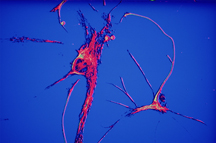

“This is very sophisticated stuff. We are interested in specific cells in the brain in very early stages of Alzheimer’s because what we are trying to do is find ways to attenuate the initiation of the disease,” says Bazan.” I believe that is the therapeutic challenge in conquering Alzheimer’s disease.”“I had done several smaller studies just working with the images and the sketches that I had made and they weren’t living to me; they were static,” Nicoll adds. “To see these real examples of actual brain tissue actually experiencing Alzheimer’s or showing signs of Alzheimer’s on a microscopic level is critical to the understanding and development of these pieces. The greatest artists throughout history worked from life. It’s really, really challenging to create an authentic work of art without actually witnessing it in person. It’s one thing if you start it, and then finish it in your studio afterwards. But that experience of seeing it with your own eyes is invaluable. You can’t replicate that.”

“I needed there to be a key protagonist for the work who was experiencing these things in his or her brain in order to bring the data and facts to life,” says Nicoll. “Rita Hayworth really stood out to me. What I was aiming for and what we had discussed that we wanted to achieve within this piece was the idea of cinematic catastrophe within the brain, a battlefield, a cerebral minefield of things taking place within the human brain. So, to connect a golden era screen goddess to the human brain was really important for me. I felt like it was a metaphor that really stood the test. Is this a real person? Yes. Is she iconic? Yes. Do people recognize her? Can they relate to her? Can they draw connections between what is going on here and her life story? Yes, yes and yes.”